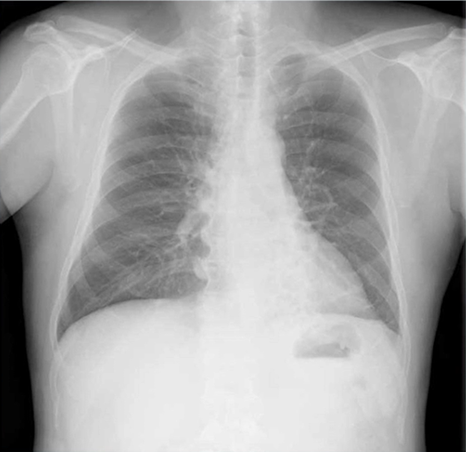

気管支拡張症の胸部レントゲン(X-p)写真

気管支拡張症のレントゲン写真はシルエットサインが陽性で、嚢胞性病変がある場合に疑えます。気管支の拡張や壁の肥厚が見える場合にも鑑別に挙げていきます。特徴を共有し…

この写真を見たら何を考えるでしょうか? 所見としては、心陰影はシルエットサイン陰性、下降大動脈はシルエットサインは陽性、左横隔膜はシルエットサインは陽性です。 …